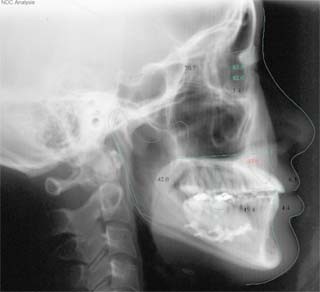

外科症例(アゴの輪郭でお悩みの方) 下顎前突

装置撤去です。動的処置は2年弱でしたので、通常のマルチブラケット治療とそれほど治療期間は変わりません。しかしながら、わずかな正中のズレが残ってしまいました。大きくは改善したのですが、左右のズレというものは、比較的、後戻りが現れやすい問題です。筋肉の影響によるものや、咬合平面の傾斜が左右的に水平でない事などが関係しているような気がします。今後は保定治療に移行し、数年にわたって咬合の安定状態を管理していきます。